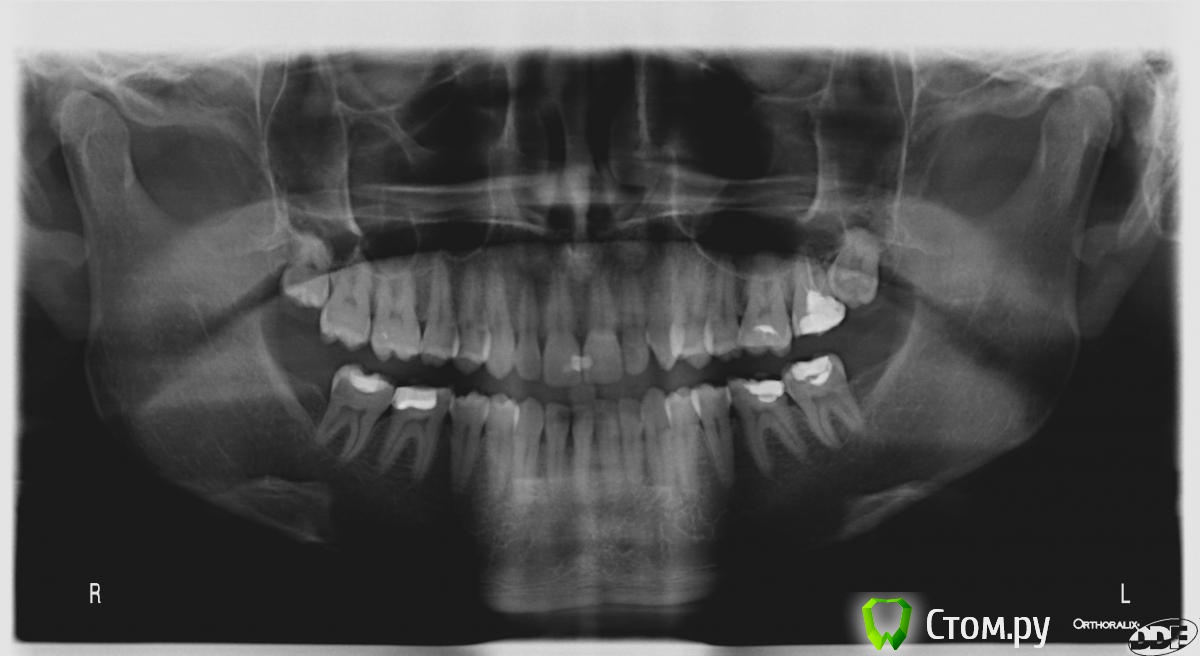

Skip Опубликовано 13 апреля, 2014 Поделиться Опубликовано 13 апреля, 2014 Первично, мне кажется, боли стали появляться в октябре 2013, после того, как стоматолог попросил меня сильно сжать больными зубами пластинку для того чтобы сделать рентгеновский снимок. Речь идет о зубах 6-7 слева, а сверху или снизу - непонятно. После этого на протяжении полугода боли активировались каждый раз после очередных стоматологичкских манипуляций (лечение 27; эндодонтическое лечение 36 и 37; удаление 28; детали и снимки находятся здесь: http://forum.stom.ru/topic/25345-dlitelnaia-problema-s-zubami-bol-v-golove-endo/). Боль в голове теперь может существовать длительное время сама по себе без надавливания на зубы (сначала локализация была левый глаз и висок, затем в последние месяцы немного сместилось в левую часть лба, более редко - левая часть затылка). При манипуляциях с зубами боль в голове усиливается. После манипуяций с зубами боль сначала усиливается, затем ослабляется медленно, в течение примерно двух недель каждый раз. Если зубы разомкнуты, то боль не исчезает сразу. Боль в глазу и головная боль проходят вместе. Давление в ушах при этом не проходит. У меня следующая версия. В данном случае, мы имеем сейчас взаимодействие двух факторов. С одной стороны, один местный фактор связан непосредственно с зубами, а именно с предшествующим эндодонтическим лечением и, как мне показалась, там слишком широко откалибровано верхушечное отверстие к/канала и, как следствие, возможно повреждение эндодонтическим инструментом периапикальной области, отсюда могут быть боли в области зуба. Что же касается неврологической симптоматики, то локализация болей весьма характерна для дисфункции ВНЧС. Дело в том, что эту дисфункцию отличает то, что она всегда имеет хроническое начало и только со временем может приобрести острый характер. И, как раз, одной из частых причин такого обострения, является поход к стоматологу, где пациент вынужден широко открывать рот или что-то там накусывать чрезмерно. Если боли в области сустава, жевательных мышц и, в частности ,височной мышцы с соответствующей областью головы можно легко объяснить, то локализацию боли в области глаза, а также в лобной области или верхнего края орбиты гораздо сложнее. Возможное объяснение этого явления следующее. Хотя Ваша ОПТГ и не может служить объективным исследованием в отношении суставов, для этого необходимы другие исследования, но даже на этом снимке можно заметить смещение средней линии нижних центральных резцов влево. Это говорит о том, что и вся нижняя челюсть смещена в эту же сторону и, соответственно, мыщелок при этом позиционируется кзади в суставной впадине. Такое позиционирование мыщелка нарушает его правильное положение по отношению к суставному диску, что приводит к перерастяжению связочного аппарата сустава. Поскольку при дистально смещённом мыщелке увеличено механическое и гидравлическое давление в заднем отделе сустава, то это приводит к механическому сдавлению и ограничению циркуляции крови поверхностной височной артерии, которая начинаясь от наружной сонной артерии проходит сзади и в непосредственной близости от капсулы сустава. http://i7.pixs.ru/storage/1/4/7/deepfacial_4347054_11668147.jpg Гистохимические потребности височной мышцы, находящейся в результате парафункциональной активности в постоянном гипертонусе, постоянно требует большего прилива крови для питания и удаления продуктов метаболизма, образующихся в результате молочного ацидоза. Однако, в результате давления сустава на височную артерию, этот приток крови ограничивается, поэтому потребности мышцы всё возрастают и возрастают. Ощущая этот дефицит крови, наружная сонная артерия расслабляется немного, чтобы обеспечить прохождение большего объёма кровотока. Но, этого всё равно недостаточно и даже увеличенный кровоток не достигает своих целей в далёких периферических отделах височной мышцы. Собственно то, что Вы ощущаете шум в ушах, это и есть шум этого усиленного кровотока. И тут начинается самое интересное. Этот увеличенный кровоток начинает распространяться через другие ветви, отходящие от сонной артерии. Давление повышается в верхнечелюстной артерии и дальше по её ответвлениям - средняя менингиальная артерия, которая идёт не только к височной доле головного мозга, но также имеет анастомозы со слёзной артерией, которая является частью комплекса глазной артерии. http://i.pixs.ru/storage/2/2/3/Gehirn2jpg_8452554_11668223.jpg Таким образом области, на которые распространяются боли и описываемые большинством пациентов с проблемами ВНЧС - супраорбитальная область, лобная или глубоко в височной области - все связаны с группой артерий, которые почти непосредственно отходят от проксимального конца верхнечелюстной артерии. Вы спросите, а почему всё-таки болит? Дело в том, что артерии очень чувствительны к повышенному давлению в них и ноцицептивная болевая возбудимость здесь очень высока. Эти "сосудистые головные боли", как их принято называть, будут длиться пока Природе, наконец, не удастся удовлетворить потребности височной мышцы. Можно долго ходить по невропатологам, психиатрам, начать принимать антидепрессанты и прочую химию, которые немного затуманят мозги, но проблему то не решат. А достаточно лишь, всего-то навсего, провести в этих случаях репозицию мыщелка вниз и вперёд в суставной впадине, устраняя таким образом давление мыщелка на задисковые ткани, также устраняя классические симптомы этих типов интенсивных головных болей, причём с высоким процентом успеха. Конечно же, существуют и другие системные этиологические агенты, которые способны дать клинику головных болей типа мигрени. Но, часто диагноз нетипичной мигрени трактуется врачами неправильно, когда фактически истинная причина симптомов пациента - не правильно сидящий мыщелок! 5 1 Ссылка на комментарий